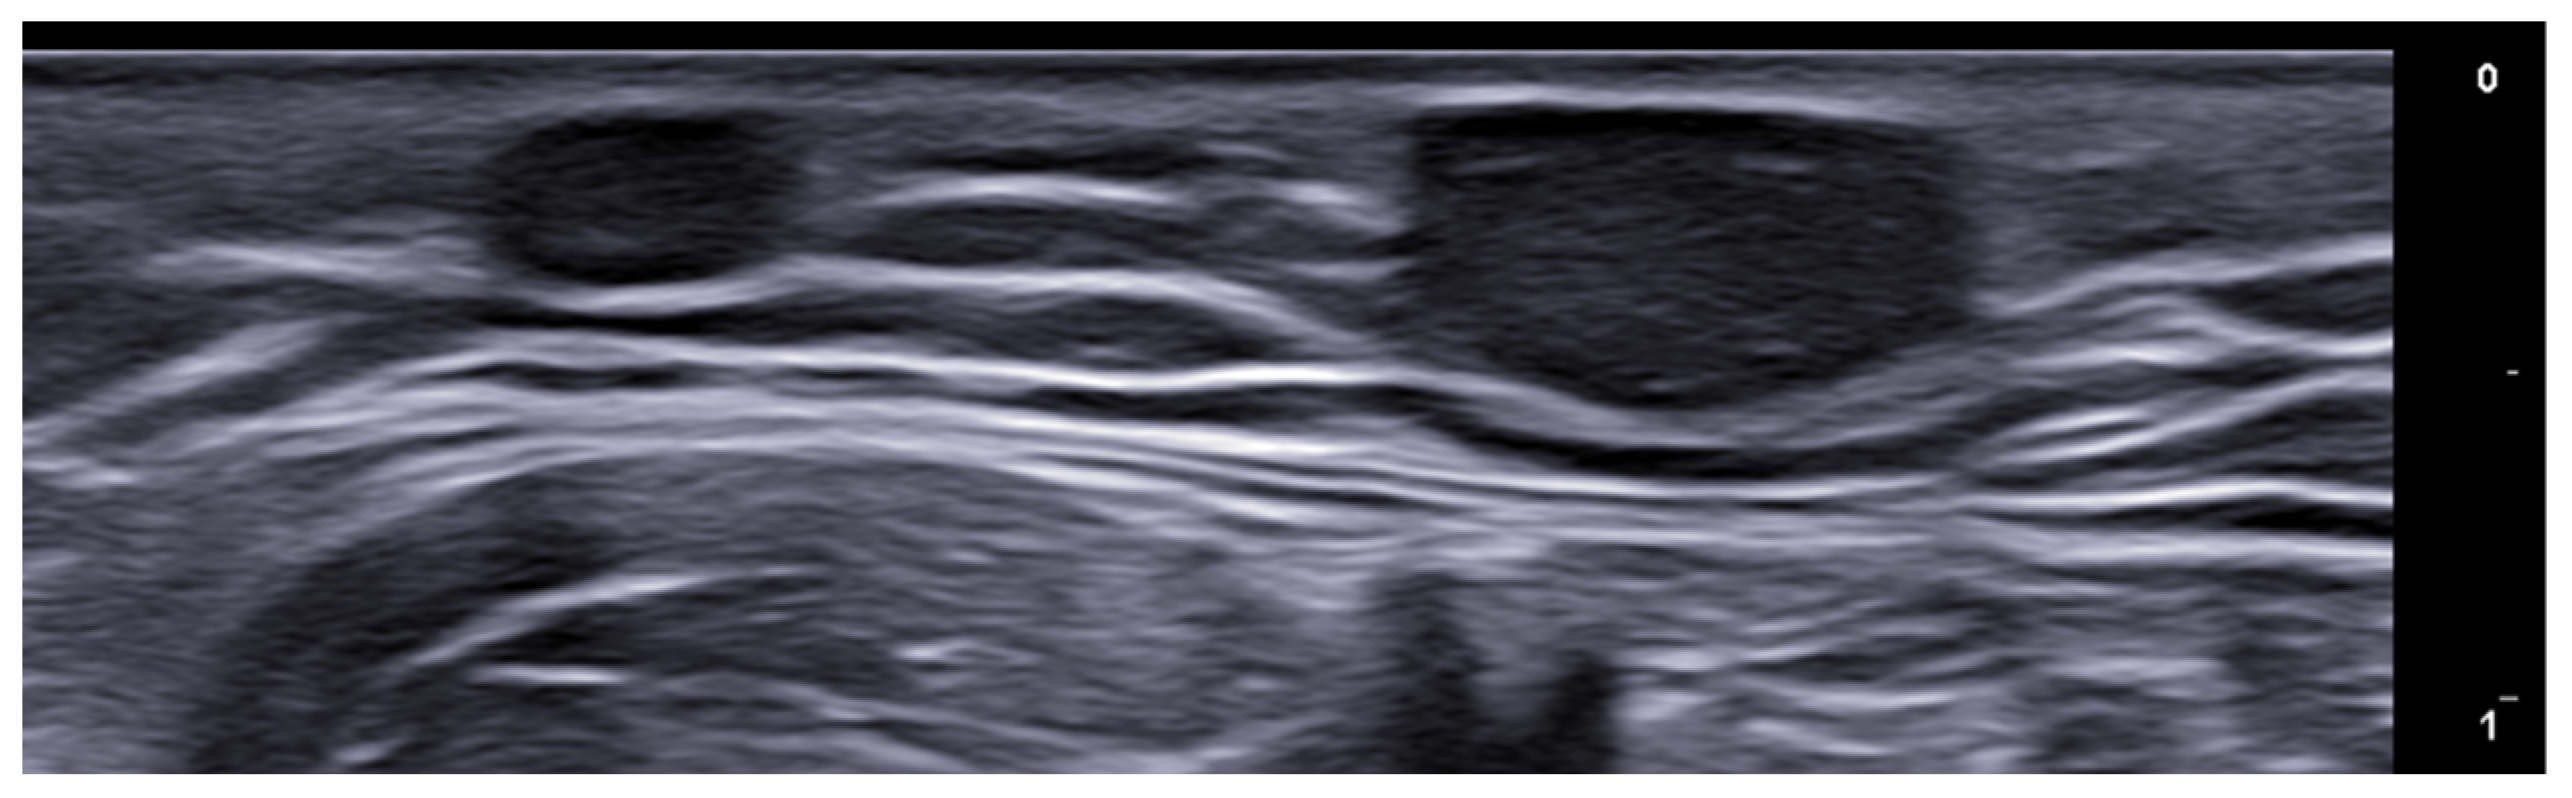

- Cheng, X.; Li, J.; Zhou, G.; Liu, Y.; Lu, X.; Wang, N.; Liu, H.; Zhang, F. High-Frequency Ultrasound in Blistering Skin Diseases: A Useful Method for Differentiating Blister Locations. J. Ultrasound Med. 2017, 36, 2367–2371. [Google Scholar] [CrossRef]